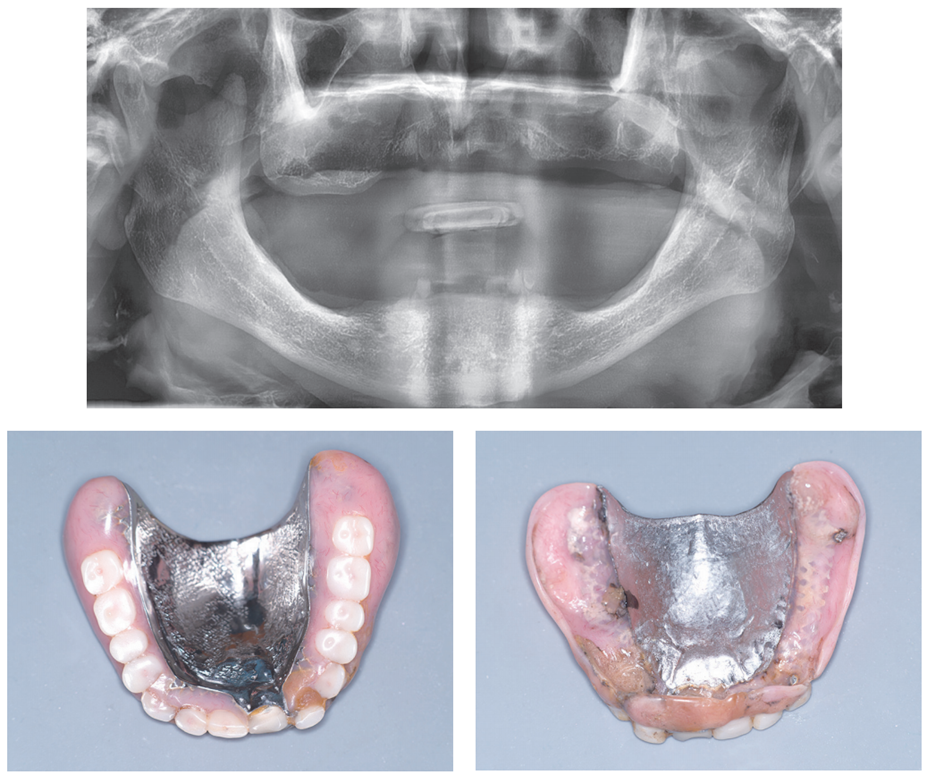

환자는 70대 중반의 남성으로 60대에 상·하악 부분틀니를 제작해서 지금까지 사용하고 있다.

상악 앞니를 5년 전에 빼고 틀니를 수정하였다.

Surveyed crown으로 이용된 하악 전치부 보철이 빠진 지는 3년 정도 되었다고 하였다.

잔존치근 발치 후 상·하 완전틀니를 계획하였다.

파노라마 방사선사진에서 보면 상악 전치부 치조골은 흡수가 심하고, 하악 전치부 치조골은 상방으로 돌출되어 있다. 또한 상악 구치 부위 치조골은 하방으로 돌출되어 있고, 하악 구치부 치조골은 심하게 흡수되어 있다.

세 번째, Kelly의 combination syndrome

Max. tuber osity가 하방으로 내려오고, 하악 구치부 치조제흡수가 심하게 진행되는 증상입니다.

파노라마 사진과 모델 진단에서 Kelly’ combination syndrome 상태를 확인하였다. 이런 증례에서는 완성 틀니 장착 후 하악 구치부에서 지속적인 통증을 호소한다.